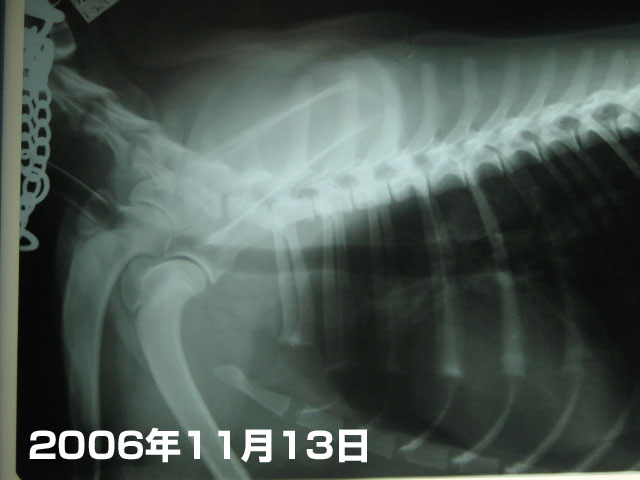

これは2006年11月13日。不妊手術の歳に撮ったレントゲン。

気管ののど元にはまだ麻酔チューブが入っている状態なので、のど元の気管の太さが確認できなかった。

頚椎の下に沿って黒く写っているホースみたいなのがもいたんの気管。

太さや形に問題なし(^-^)v

次に肺。

1枚目の2006年11月13日、不妊手術の歳に撮ったレントゲンと比べてみるとわかるけど、

肺(肋骨にくるまれた中央の下の方の白っぽい部分)が、少々【石灰化】して?白っぽくなっている。

たぶんそれはホルモン(上皮小体?)が不安定な状態らしく、カルシウム分は控えたほうがよいでしょうって。